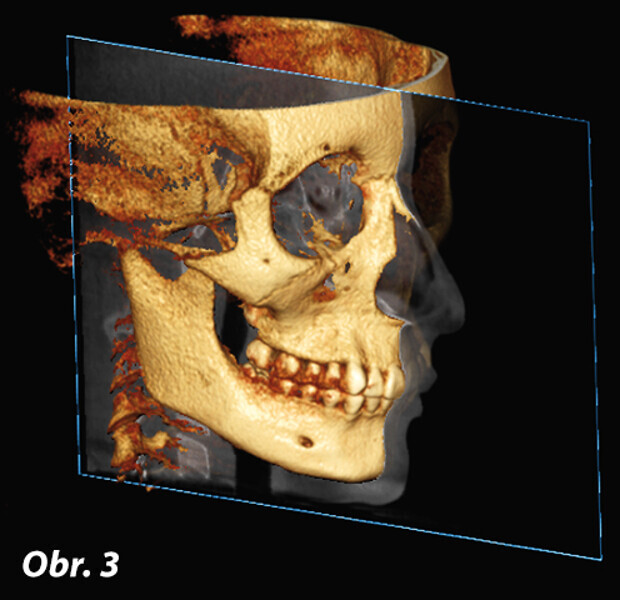

Význam 3D zobrazovacích systémů v současné ortodoncii